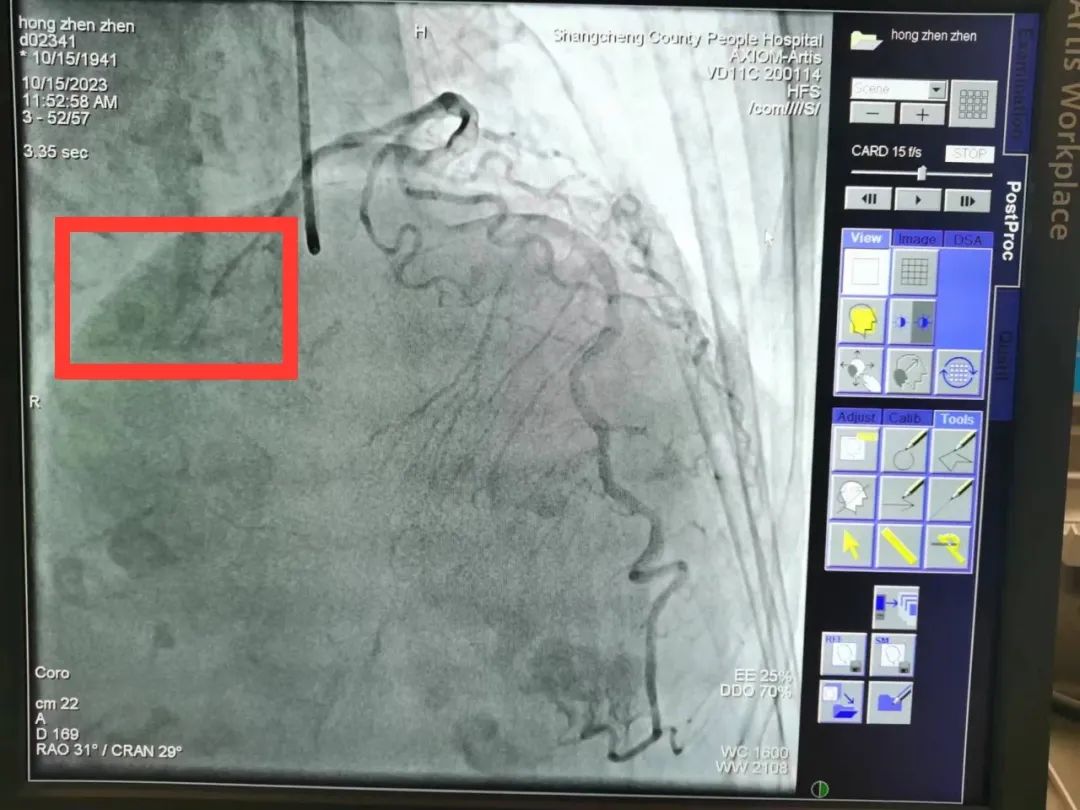

然而,患者急诊冠状造影结果显示:左右冠脉主干血管未见明显狭窄,无法确定“罪犯血管”,但是患者心电图提示下壁仍然持续抬高,胸痛症状得不到缓解,病情扑朔迷离。一直在导管室指导的熊晨晖主任仔细观察了影像结果,发现患者右冠细小,回旋支远端可为右心供血,可能为“功能性右冠脉”,所以考虑回旋支远端为“罪犯血管”。随即邀请郑州大学第一附属医院心内科教授远程会诊,教授同意熊主任的观点,认为左旋支可能是“罪犯血管”,但认为回旋支远端较细、且供血区域局限,介入手术治疗获益不能肯定,可以尝试手术看看效果,也可以先药物治疗。

回旋支未见明显狭窄,远端可见慢血流